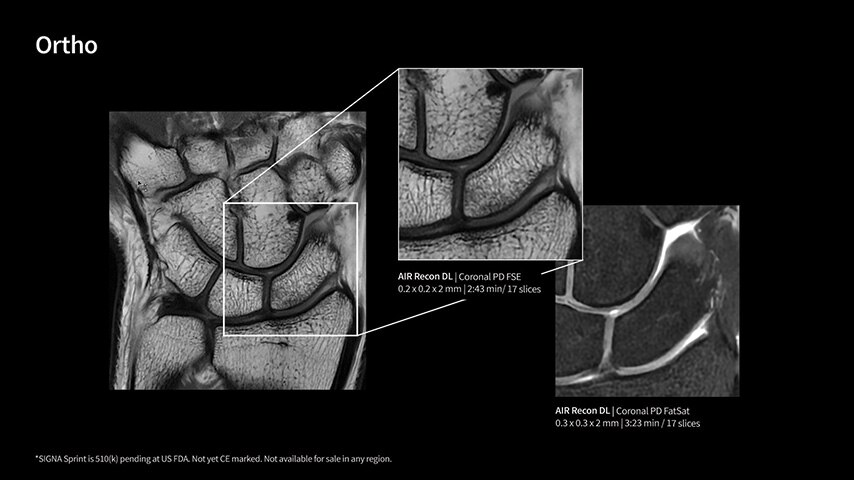

Imaging capabilities to unlock the power to explore further

High gradient performance

The growing clinical need within oncology and cardiology requires an MRI scanner that can rise to the challenge. With a high gradient performance of 65/200, SIGNA Sprint helps deliver crystal-clear imaging for ultimate diagnostic confidence. Improved signal-to-noise ratio (SNR) and diffusion, with deep-learning solutions that could enhance diagnostics and treatment response monitoring in your oncology patients.¹ Additionally, the shift from qualitative to quantitative cardiac MRI reduces the time and expertise needed to interpret scans and offers greater consistency and reliability. Helping you to unlock the power to explore further - even in your most challenging cases.

Deep-learning intelligence

Unlock your potential

With GE HealthCare's comprehensive suite of deep-learning solutions integrated into SIGNA Sprint, you can unlock the full potential of your MRI system. No need for complicated patient setups or imaging protocols. The exceptional intelligence of our AI solutions offer multiple benefits, with AIR Recon DL giving pin-sharp images, Sonic DL accelerating scans up to 12x, and AIR x enabling automated slice placement. All helping to enhance your department’s workflow efficiency, increase patient throughput, and get the diagnostic clarity you need, faster.¹ Meaning you can spend more time on what truly matters—personalized patient care, enabling optimized treatment plans and treatment response monitoring—ultimately, supporting better clinical outcomes.